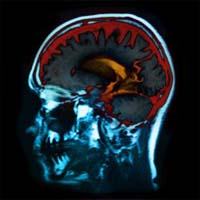

After the scan is complete a control has been formed which can be compared with activated regions of the brain while performing visual memory tasks. [9] Poor memory after damage to the brain is usually considered to The findings revealed that there may be binge-drinking related ... Read Article

Binge drinking is especially dangerous because the teen brain is much more vulnerable to damage. Alcohol’s effect on coordination, hand-eye movement, speech, and emotional control also ... Access Document

College Students At Risk During Alcohol-Related Blackouts

Binge Drinking Effects That Last A Lifetime .mpg - YouTube